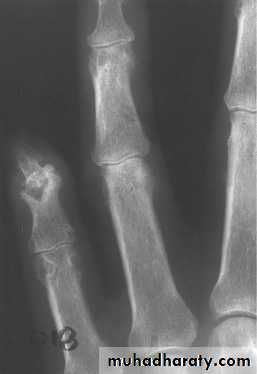

Radiographs are often normal during early episodes of gout. They may be useful to differentiate other problems such as fracture or infection from acute gout. Often, soft tissue swelling is the sole radiographic finding in early gout.

In the later stages of untreated disease, clinical manifestations characteristically change. Acute attacks are more often polyarticular. The intercritical stage shortens, and repeated joint damage results in permanent deformities, loss of motion, chronic pain, and tophi.

Polyarticular gout occurs in late-stage disease, although some patients present earlier with polyarticular attacks. Intercritical stages are short or non-existent and involvement of atypical sites including the upper extremities, the spine, and axial joints may ensue. After repeated attacks in a single joint, deformity and loss of motion may occur.

Tophi are deposits of urate embedded in a matrix composed of amorphous urates, lipids, proteins, and calcific debris . Tophi are usually subcutaneous, but they rarely occur in bone and other organs including the heart valves and the eye.